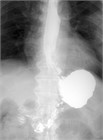

1. 嘔吐、腹痛、腹部膨満、便秘などを主訴に受診した場合には、腸閉塞の診断を行い、その原因として、内ヘルニアを念頭に置いておく必要がある。内ヘルニアによる絞扼性腸閉塞は重篤化するため、早期診断が重要である。早期診断には造影CTが有用であるため、行うことが勧められる(推奨度1 O)

1. 内ヘルニア・横隔膜ヘルニアと診断がつき次第、手術適応である。緊急的に行うか、待機的に行うかについては、造影CTで腸閉塞の状態を把握する必要がある。陥入した腸管を整復し、ヘルニア門を閉鎖もしくは開放する手術を行う(推奨度2 C)

1. 食道裂孔ヘルニアのある場合には胃食道逆流症(GERD)の合併率が高い。胃液の逆流による逆流症状を認め、治療はまず胃酸分泌抑制としてPPIによる治療を行う。内服治療だけでなく、食事指導、生活指導も重要である(推奨度1 M)